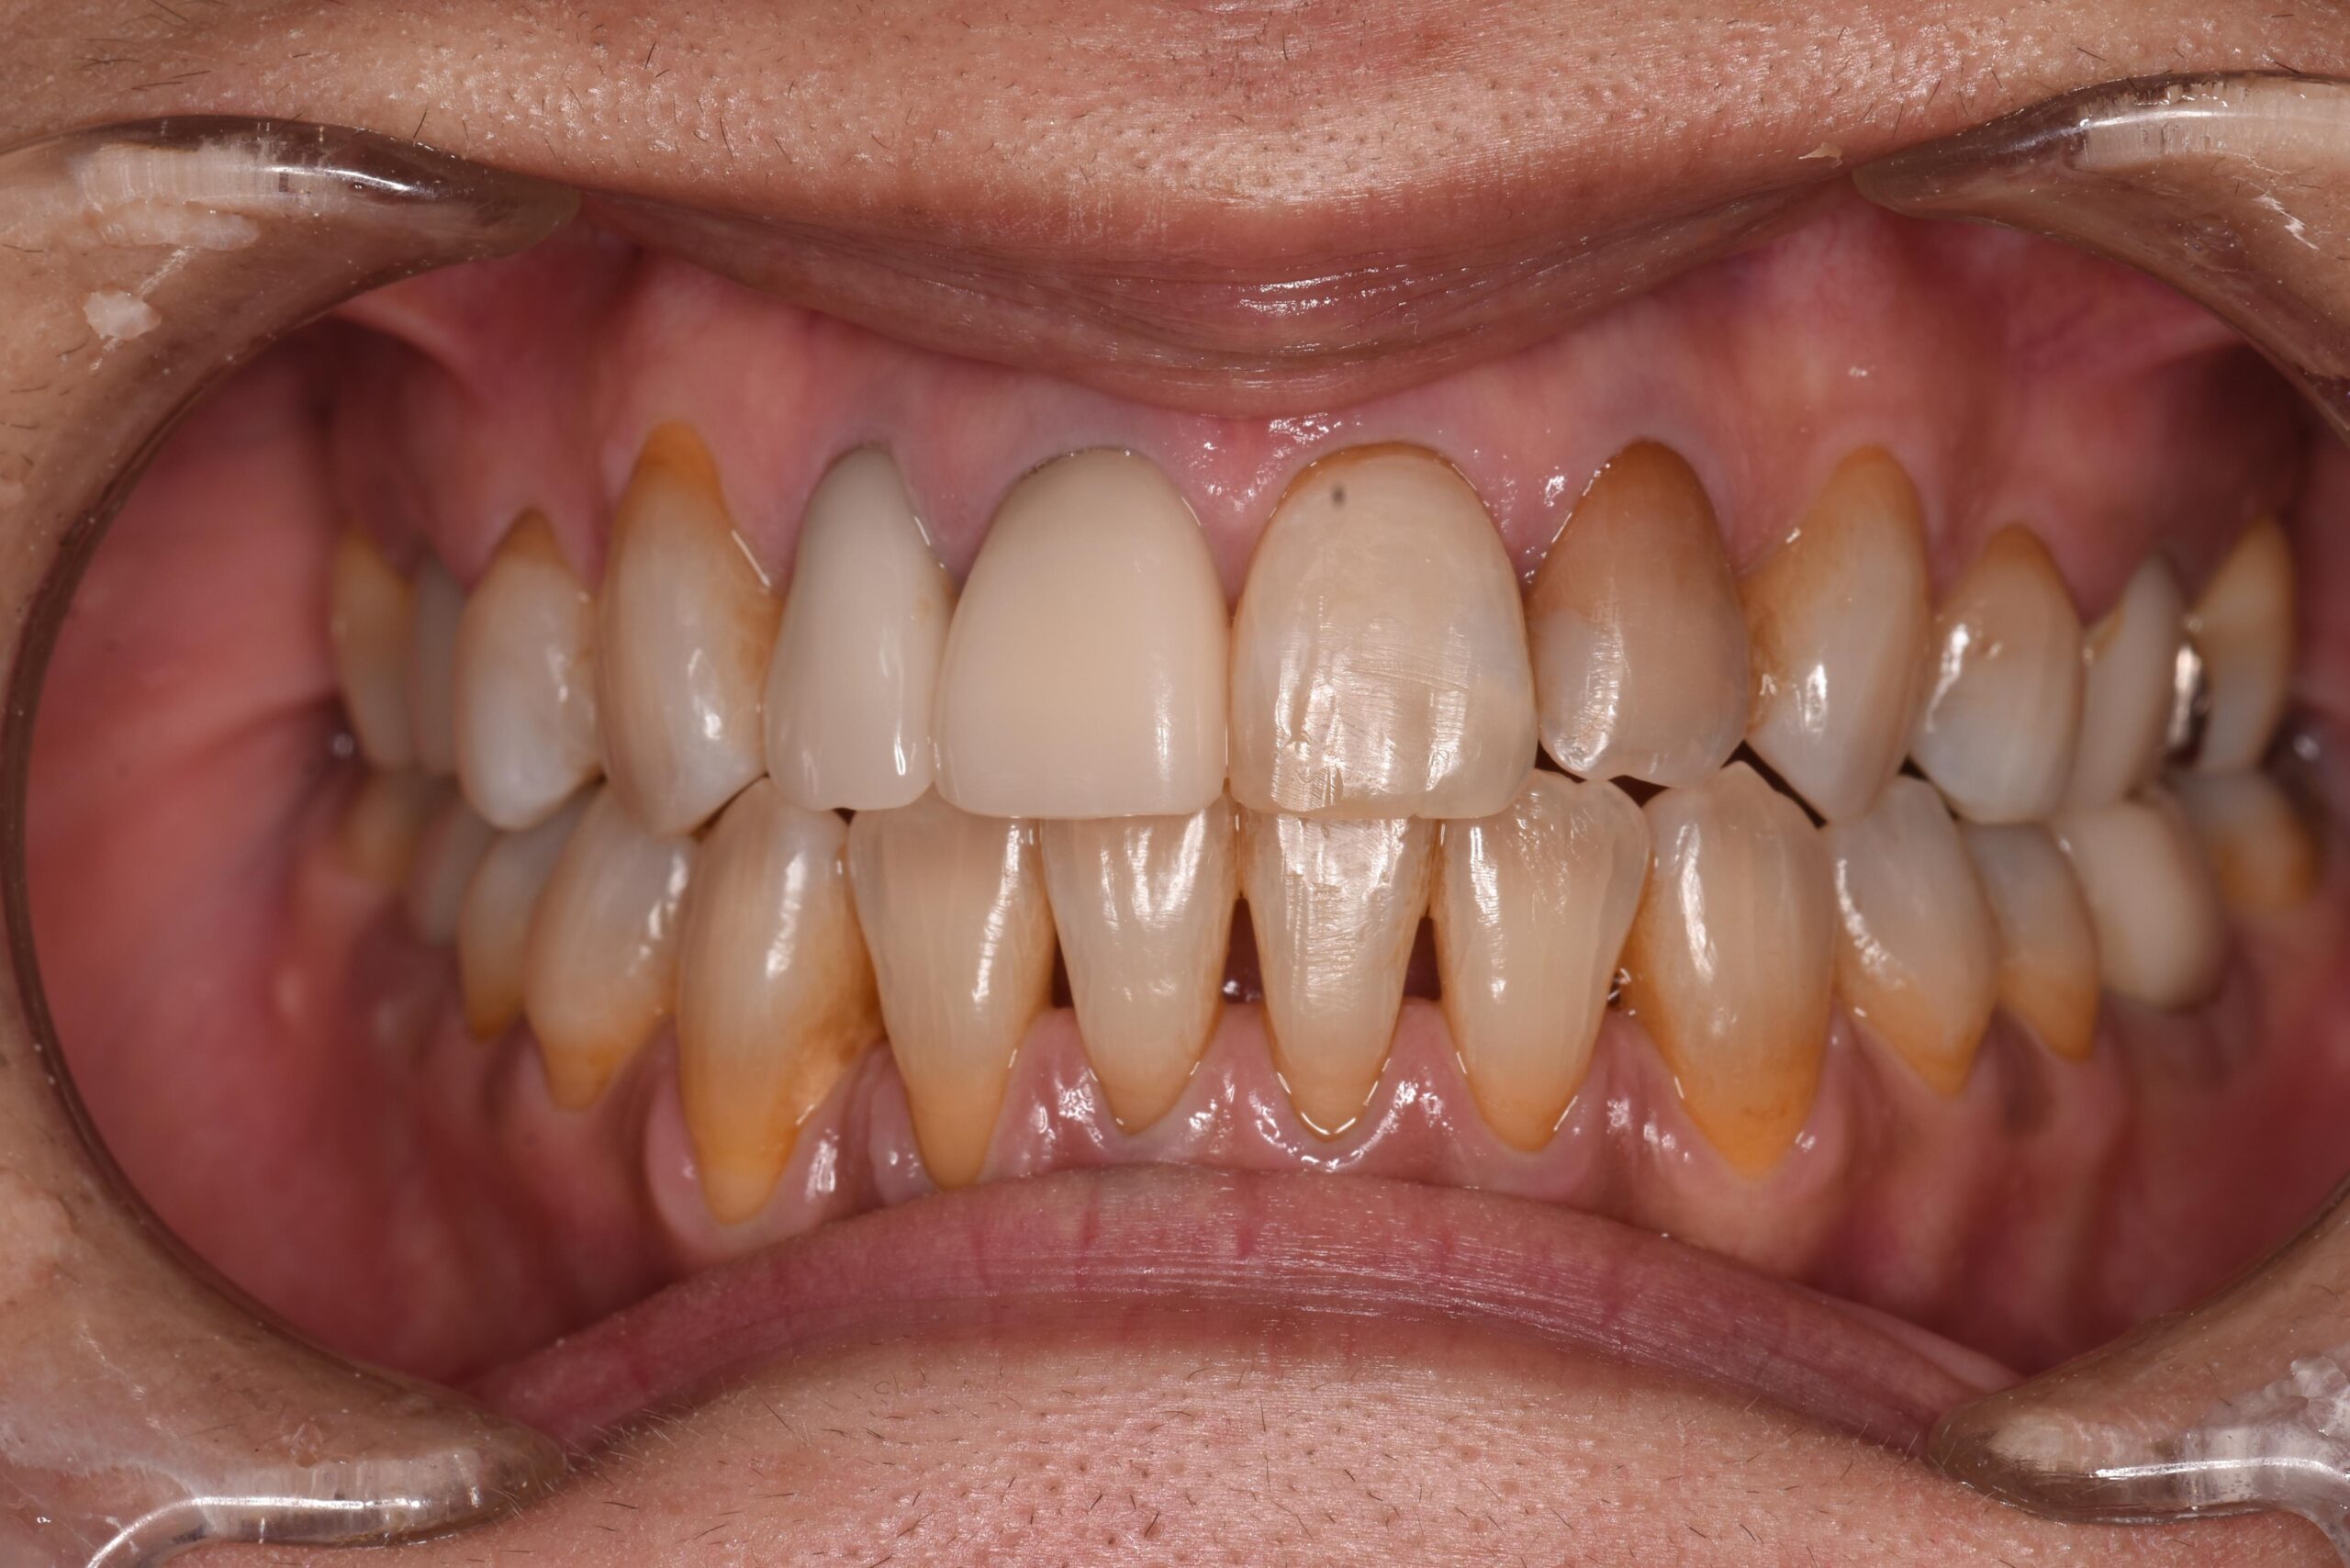

矯正治療の目的の多くは、歯並びを綺麗にすることだと思いますが、口元の印象が変わるだけで、相手に与える印象は大きく変わると言われています。矯正治療前は「いつも口元を隠して笑っていた」とおっしゃっていた患者様が、治療後に満面の笑みで「自信が持てるようになった」とお話しくださります。

歯並びがガタガタしていたり、重なっていたりすると、どうしても磨き残しによる虫歯や歯周病のリスクが高まります。綺麗な歯並びは、歯磨きがしやすくなり虫歯や歯周病予防にも繋がります。